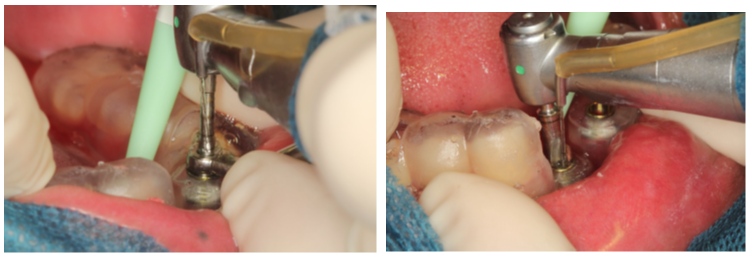

Após três meses, foi realizado enxerto gengival livre e o aprofundamento de vestíbulo.

Na sequência de imagens, podemos perceber a formação de gengiva inserida e a devolução do vestíbulo que tinha sido totalmente perdido.

A cirurgia guiada foi fundamental na resolução desse caso, pois uma cirurgia com incisão e descolamento de tecido mole traria muitas dificuldades para a cicatrização.